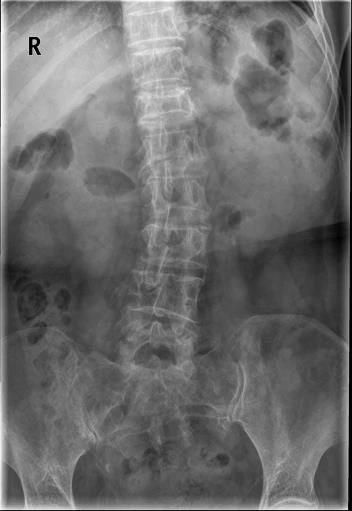

Case12:F,4y;患儿颈部活动受限1个月。